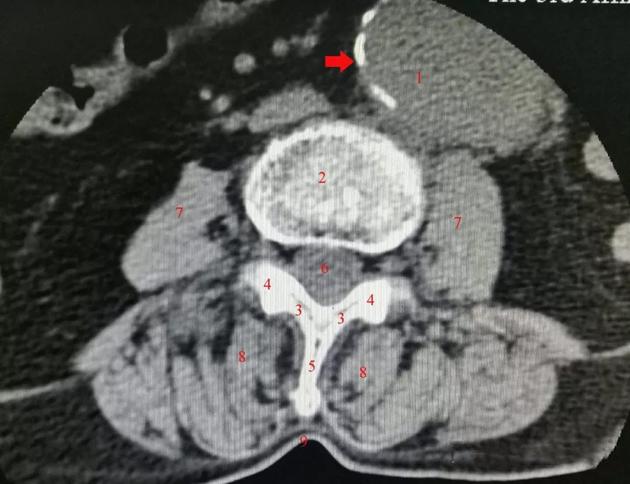

2为椎体;3为椎板;4为关节突;5为棘突;6为硬膜囊;7为腰大肌;8为竖脊肌